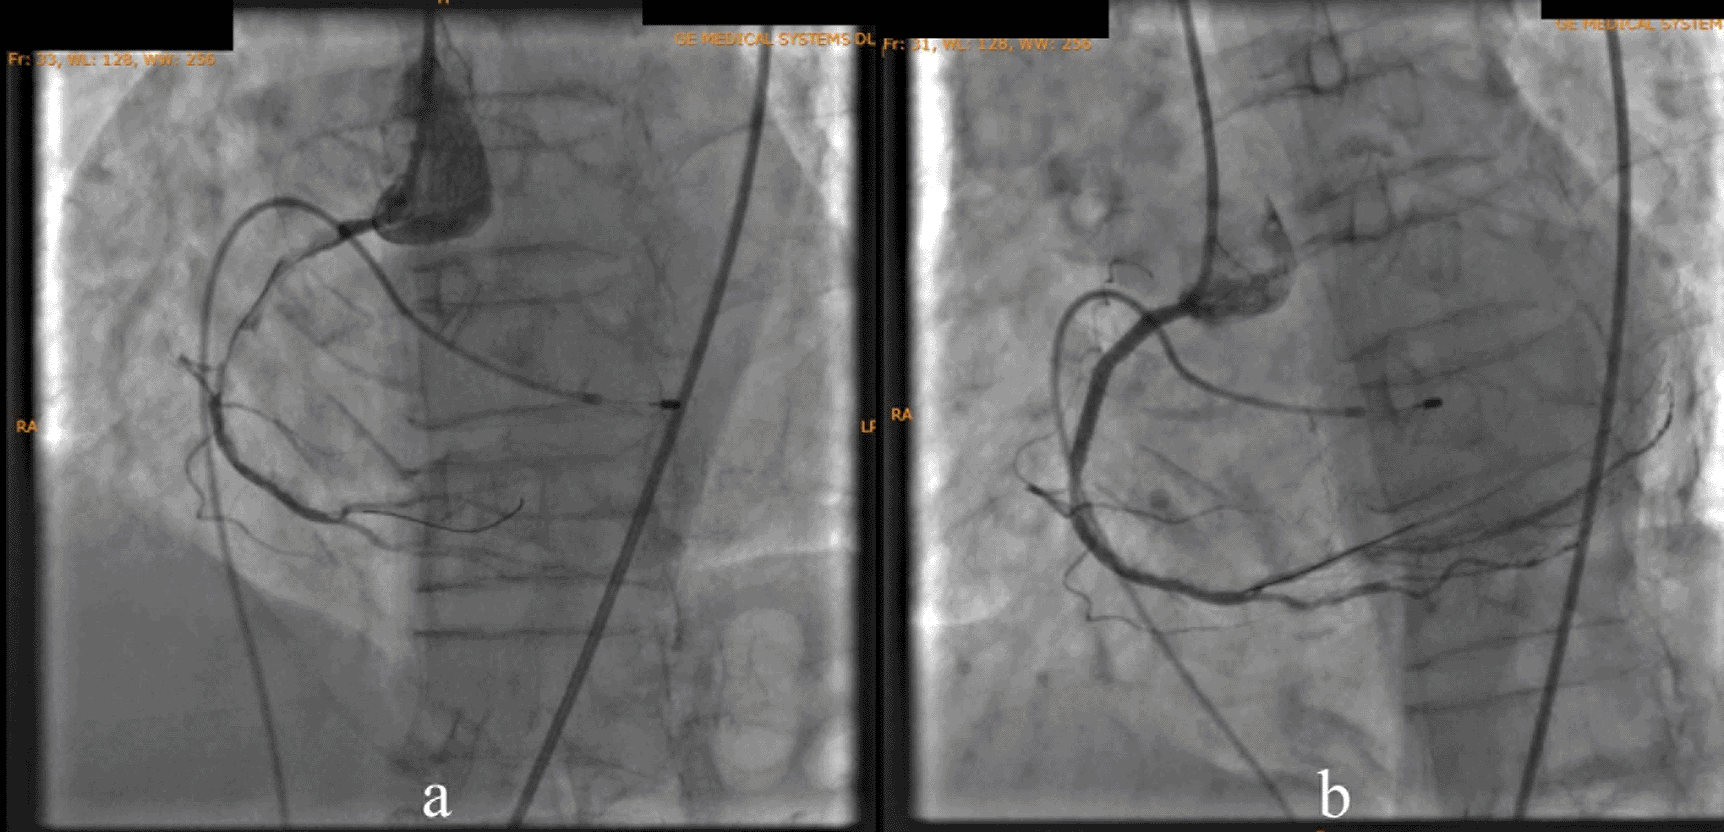

According to the DCA, the total occlusion was at the proximal right coronary artery (RCA) (Figure 2). There was insignificant stenosis in the proximal-mid left anterior descending artery. Besides, there were no stenosis on the left circumflex artery and the left main coronary artery. Primary PCI at the RCA was conducted using drug eluting stent (DES) promus and then thrombolysis in myocardial infarction (TIMI) grade 3 flow was shown at the RCA (Figure 3). Electrocardiography was also conducted after the installation of the pacemaker (Figure 4).